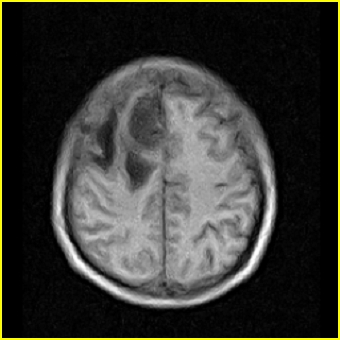

男,45岁,头部剧烈疼痛伴呕吐5天。

右侧额叶见较大的类圆形长t1信号环绕等t1环影,长t2信号环绕短等t2环,周围见明显水肿占位征,中线结构左移,男,45岁,头部剧烈疼痛伴呕吐5天。

右侧额叶,见一占位病灶,t1像病灶、水肿长t1;其间为短t1环行信号。t2像病灶、水肿长t2,其间为短t2环行信号。占位效应明显,中线左移,右测脑室受压闭塞。结合患者发病较急。首先考虑:右侧额叶脑脓肿形成。鉴别:1、转移瘤,多发多见2、胶质瘤。建议增强

t1加权肿瘤呈低信号,肿瘤壁呈等信号.t2 加权时肿瘤呈高信号,肿瘤壁呈等信号.

考虑1脑脓肿.2恶性胶质瘤.